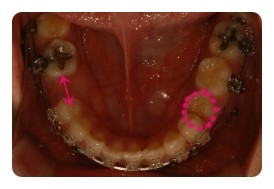

( 하악비교 )

▲ 7월 - 3개월차, 오른쪽유치 2차삭제

▲ 10월 - 6개월차

왼쪽 결손치는 발치한지 몇년되엇기때문에 이미 잇몸뼈가 굳어져서 진행이 더딜수밖에 없다고해요

그동안 꿈쩍도 안하고잇는줄 알앗는데 비교해보니 이정도면 뭐 기특하네요 ㅋㅋ

그에비해 오른쪽 유치는 조금씩 삭제하면서 당기고 잇는데요

쑥쑥 잘 움직여주고 잇어서 2차 삭제까지 햇는데도 벌써 또 닫혀가고 잇어요